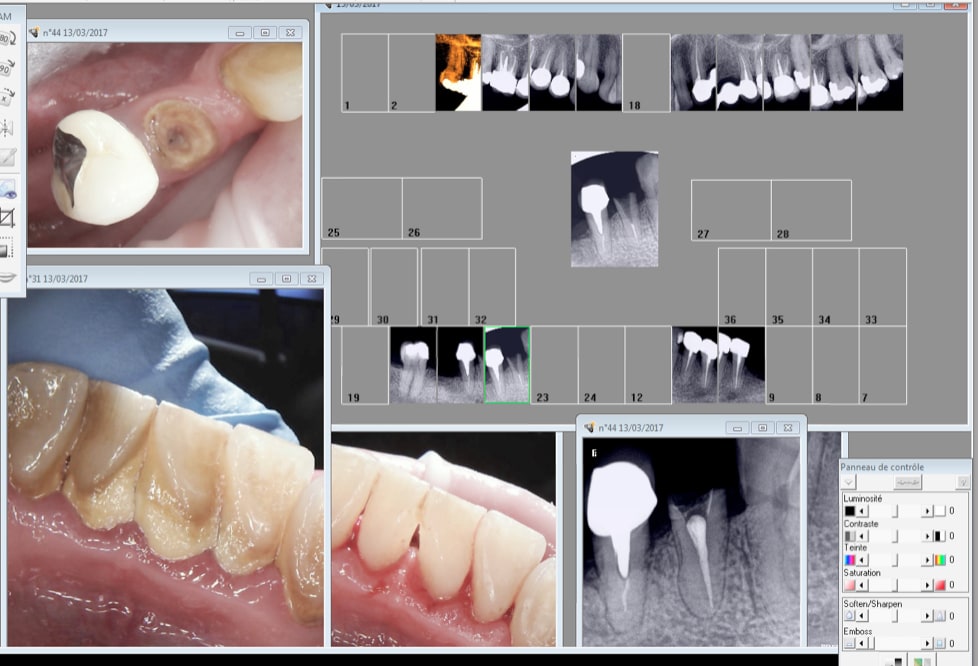

Nouveau patient. paumé sa couronne sur 44.

Status RTE 44 detartrage 30 mn.

Endo sur 17 et 2 couronnes à suivre. devis effectué.

Capture d écran 2017 03 13 18.31 - Eugenol

RTE fini ?

pas l'impression d'avoir un 2° canal ?

Je pense pas non il y aurait eu une pèche depuis longtemps.